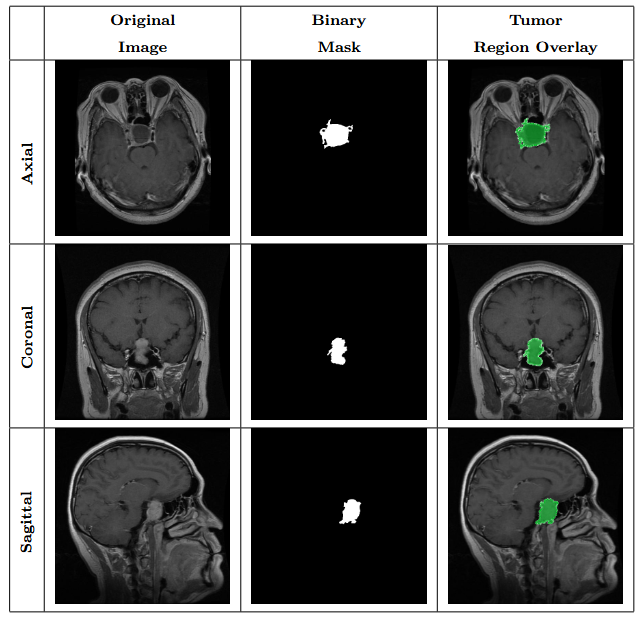

Figure 2: Samples of Pituitary segmentation across different imaging planes

2) Segmentation task:

Pixel‑wise tumor annotation task. Contains 4,793 image files with exact paired masks. Figure 2 shows an example image from the dataset together with its mask.